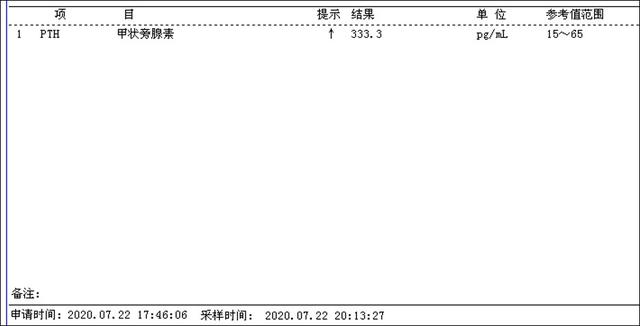

介入微创消融治疗一周后甲状腺旁腺素降为333.3pg/ml(治疗前为3300pg/ml),静脉转换口服补钙血钙正常,全身骨痛明显好转。